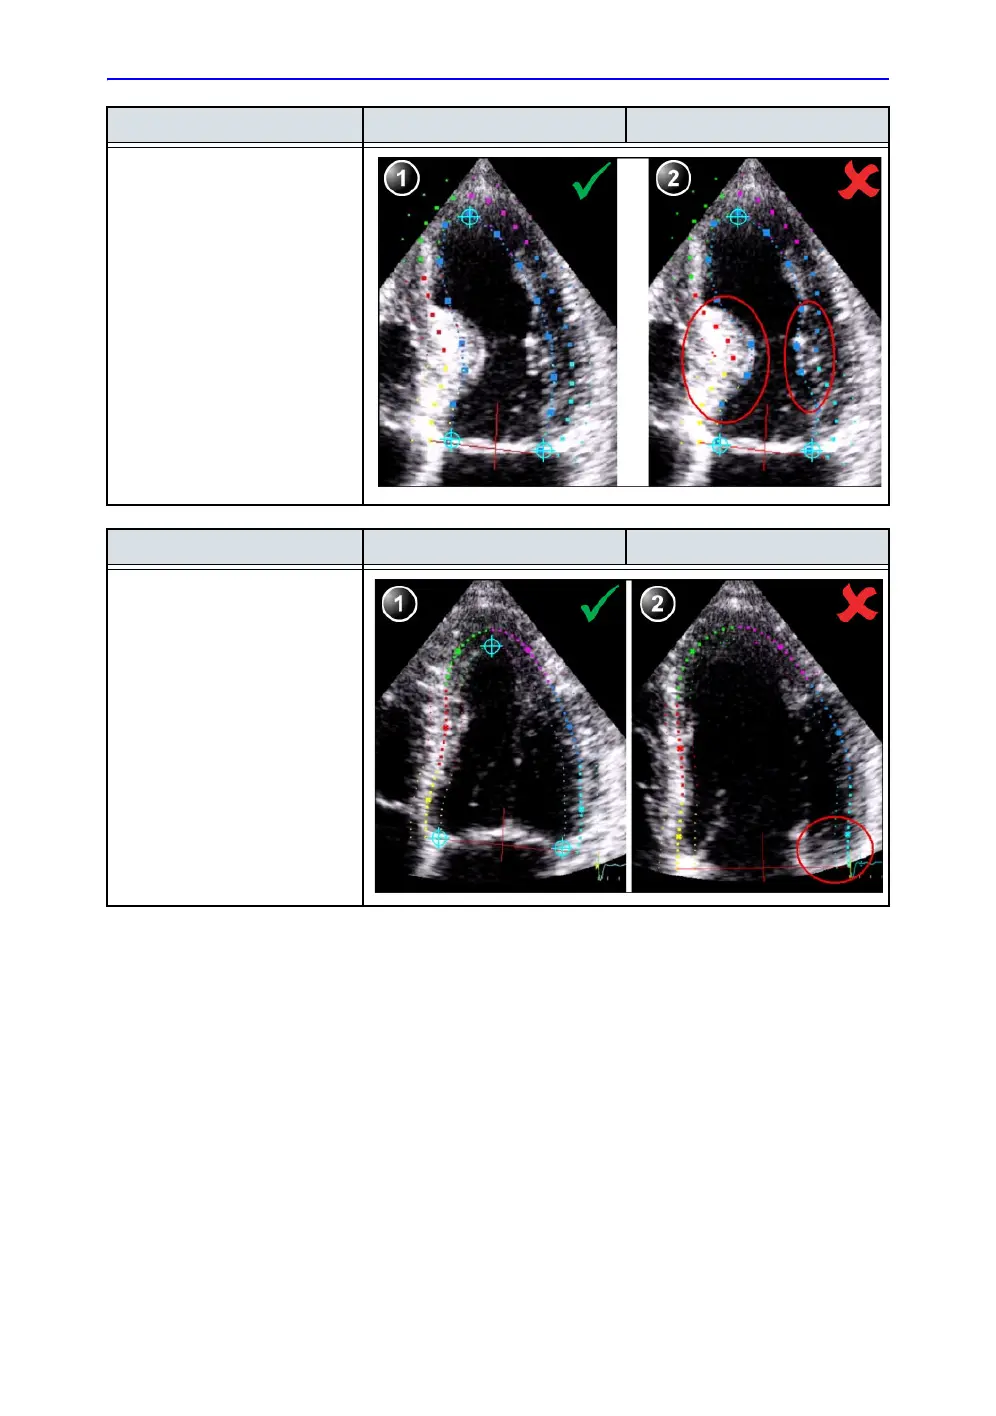

Bulges Correct Wrong

1. Correct ROI.

2. ROI should not be bulging or

follow the papillary muscle.

To edit the ROI, see ‘ROI

adjustment’ on page 8-25.

General Correct Wrong

The left ventricle must be visible

through the entire cycle.

1. End systole frame: the entire

left ventricle is displayed.

2. End diastole frame: the

annulus is not displayed.